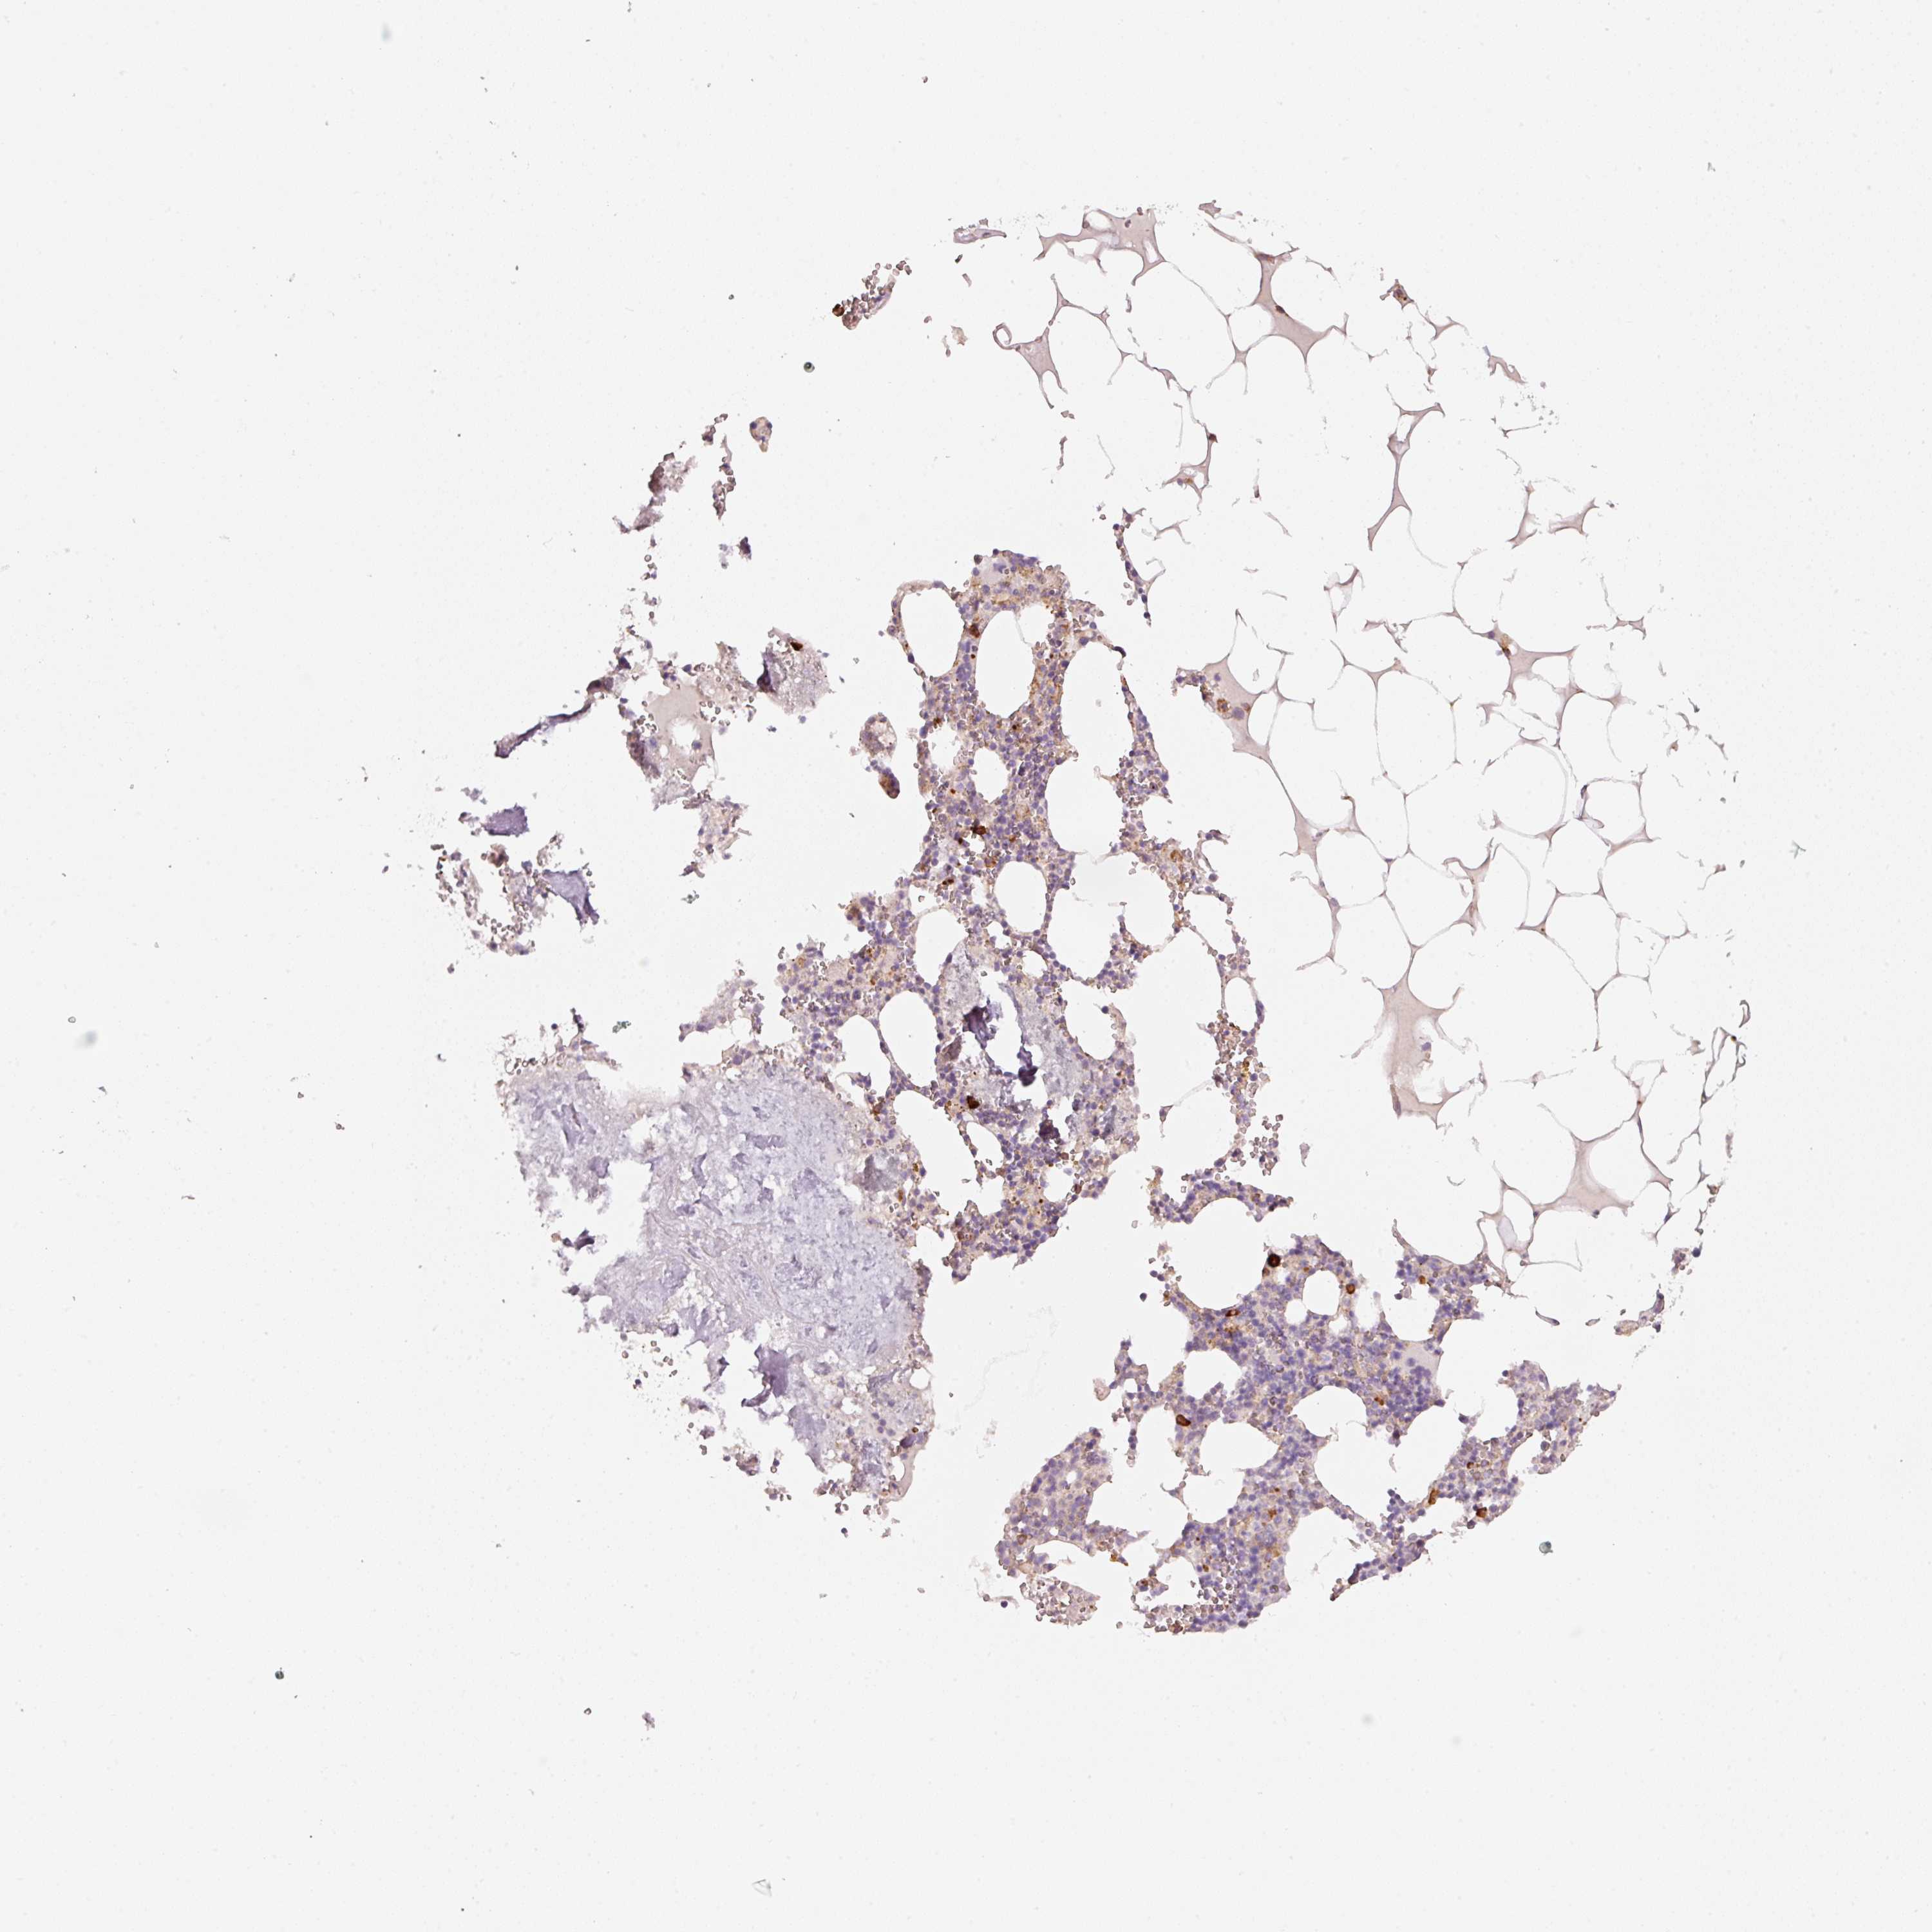

OR13C3